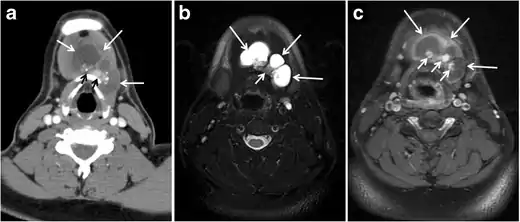

Fig. 9. A 58-year-old male patient with persistence PTC at thyroid bed with hypervascular nodal metastasis. a–c Transverse greyscale and colour Doppler neck ultrasound demonstrate hypoehoic soft tissue in the left thyroid bed (white arrow in a). There are a heterogeneous enlarged lymph nodes at level 2 and 3 with markedly increased vascularity (white arrow in b and c). d–f Enhanced axial CT images of the neck demonstrate a 2.7 × 1.4 cm hypodense soft tissue lesion anterior to the left carotid sheath (white arrow). There are left-sided enhancing abnormal and enlarged lymph nodes at cervical level 2 and 3 (black arrows).[1]